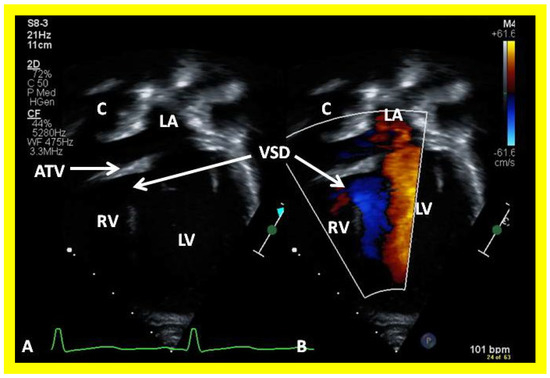

Figure 6. Selected video frames from apical four chamber, two dimensional echocardiographic views of a patient with tricuspid atresia showing an enlarged left ventricle (LV), a small right ventricle (RV) and a dense band of echoes at the site where the tricuspid valve echo should be (ATV) (thick arrow) with a closed (A) and open (B) mitral valve. A moderate sized ventricular septal defect (VSD) (thin arrow) is shown. LA, left atrium; RA, right atrium. Reproduced from Reference [29].

Applsci 11 09472 g006

On 2D echocardiography, the atretic tricuspid valve is visualized directly as a dense band of echoes at the site where the tricuspid valve should be, as shown in Figure 4, Figure 5 and Figure 6; this echo appearance is that of the most frequent muscular type of TA. This anatomy is better demonstrated in apical and subcostal four chamber views than in other views. The other anatomic types (Figure 1), namely, membranous, valvular, Ebstein’s, atrioventricular septal defect, and unguarded tricuspid valve with muscular shelf, are rare and may also be recognized on 2D echocardiography. An example of an atrioventricular septal defect type of TA [30] is demonstrated in Figure 7; in this example, a 2D echocardiogram demonstrated an ostium primum ASD with a common atrioventricular valve and a small RV (Figure 7a,b); the entry into the RV appeared to be occluded by a leaflet of the common atrioventricular valve. Left ventricular and right atrial cineangiograms confirmed these findings [30]. Evaluation of the crux cordis (Figure 8) on a 2D echocardiogram (subcostal four chamber view) may help to distinguish the various anatomic types (Figure 1) from each other. In the muscular type of tricuspid atresia, a dense band of echoes is seen where the normal tricuspid valve should be (Figure 8A). In membranous types of tricuspid atresia, a thin membrane is seen instead (Figure 8B). In both these types, the anterior leaflet of the detectable atrioventricular valve is attached to the left side of the interatrial septum (Figure 8A,B). In the atrioventricular septal defect type of tricuspid atresia, the crux cordis is abnormal and cannot be identified; the anterior leaflet of the detectable atrioventricular defect is attached to the anterior wall of the heart, and a large atrioventricular valve leaflet occludes the entry of the RA into the RV (Figure 8C). Based on these observations, it was concluded that 2D echocardiographic (and angiographic) features help to differentiate the atrioventricular canal type of tricuspid atresia from the classic muscular tricuspid atresia cases [30].

Following the demonstration of the atretic tricuspid valve, the sizes of the cardiac chambers are evaluated both by M-mode (Z scores) and 2D echocardiography; an enlarged RA, LA and LV and a small RV are seen (Figure 4, Figure 5 and Figure 6). Pulsed (not shown) and color Doppler (Figure 9) studies are helpful in illustrating right to left shunt across a PFO or an ASD.

Then, the ventricular septum is evaluated; the ventricular septum is intact in most Type Ia cases. In children with Type I (normally related great arteries), the VSD supplies the pulmonary blood flow (Figure 10) while in patients with Type II (transposition of the great arteries) the VSD allows the blood to flow into the systemic circuit (Figure 11; Figure 12). In Type I patients, the VSD is demonstrated by 2D (Figure 10A), and the left to right shunt across it by color (Figure 10B), pulsed and CW (Figure 10C) Doppler signals. The interrogation of the RV outflow tract and PA region should be performed; recording the peak Doppler flow velocity across the RV outflow tract and the pulmonary valve is helpful in identifying obstruction across these sites. The Doppler data from the VSD and RV outflow tract are also helpful in the estimating of PA pressures. In Type I babies, the 2D size of the VSD and the peak Doppler flow velocity across it are useful in quantifying the size of the VSD (Figure 10). The higher the VSD Doppler flow velocity, the smaller the defect. However, in patients with pulmonary hypertension or severe infundibular or valvar pulmonary stenosis, the VSD Doppler velocities are not reflective of the size of the VSD. Barring these exceptions, RV and PA systolic pressure may be estimated using a modified Bernoulli equation (RV/PA systolic pressure = systolic blood pressure – 4V2).